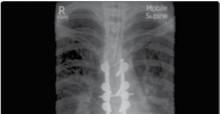

Figure 4.2 Thoracic vertebrectomy with posterior stabilisation for a solitary metastasis.